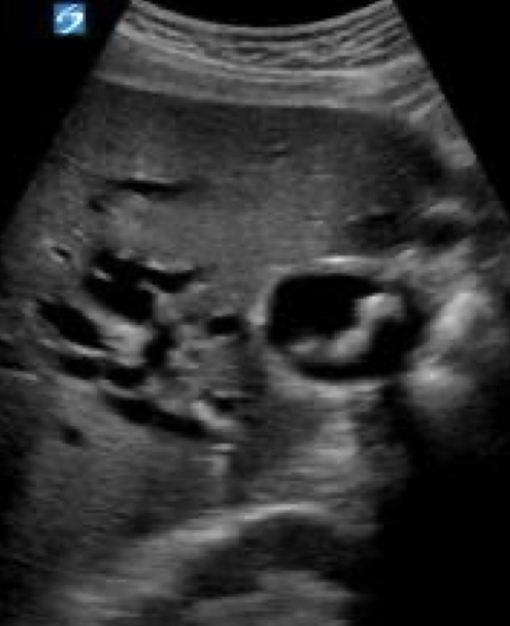

??

gallbladder carcinoma

heterogeneous mass in GB

adjacent heterogeneous liver